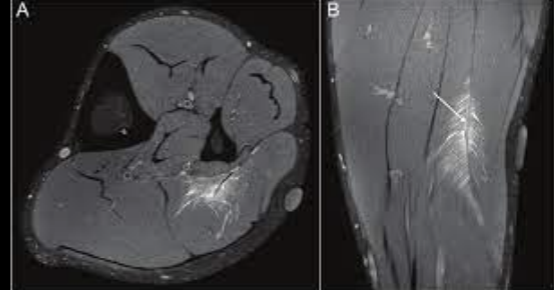

Datos de desgarro muscular en US

Edema y liquido

Disrupción fibrilar

Desgarro muscular

Grado desgarro en RM

1: hiperseñal pluma de ave

2: disrupcion de fibras

3: disrupciones completa y retracción

Grado 1 pluma de ave

Disrupción de fibras